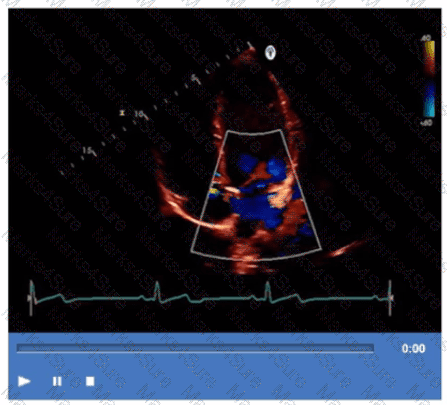

Which procedure is most appropriate for evaluation of an atrial septal defect in the presence of an atrial septal aneurysm?